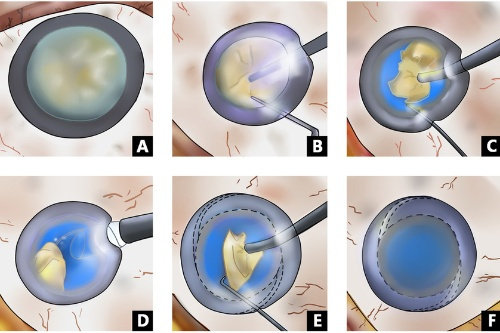

白内障手术是一种非常常见且安心的眼科手术,通常采用超声乳化技术将模糊的晶状体取出,然后植入人工晶状体以改善眼部视力。